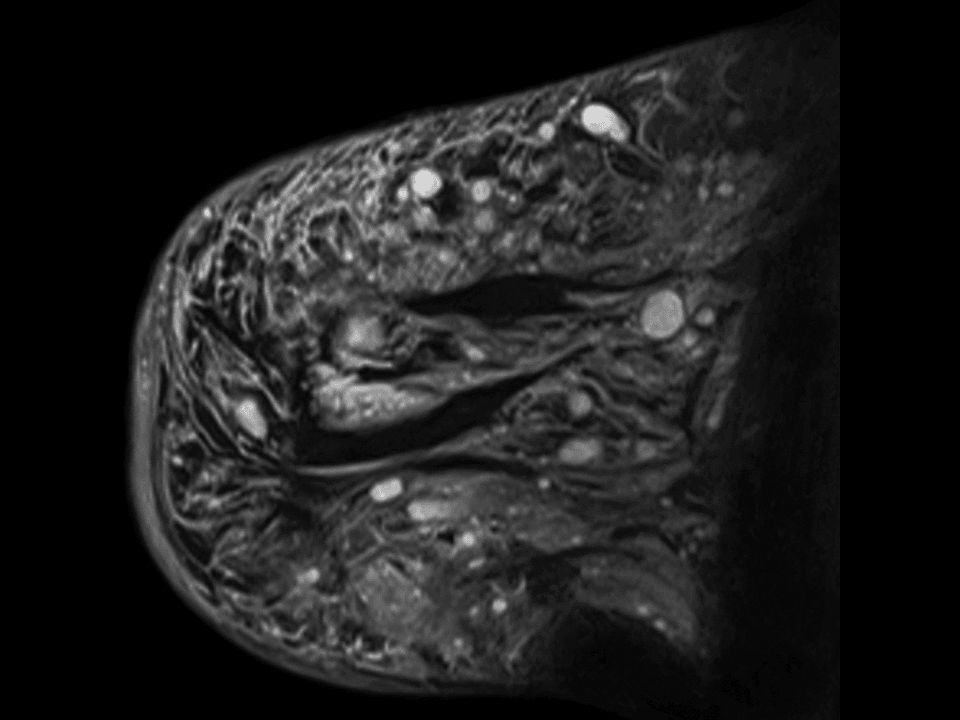

Examine ligament tears to cartilage degeneration with high-resolution imaging and a wide range of dedicated coils.